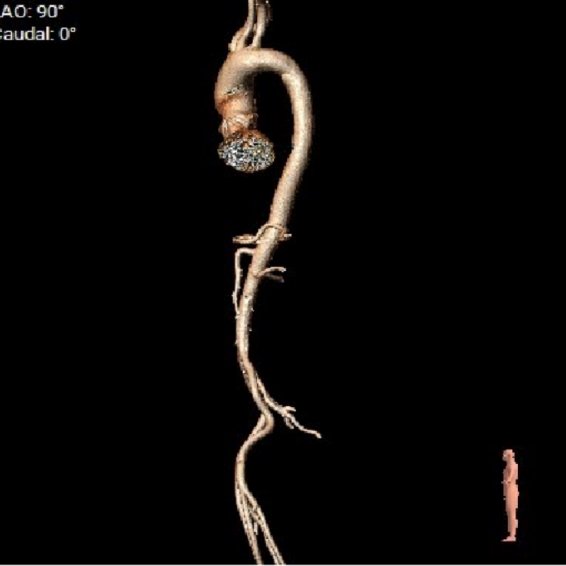

外周血管及主动脉弓解剖

● 外周入路走行适宜,腹主中下端和左右髂总散在钙化,血管内径尚可,血管内壁存在不规则纤维增厚和钙化斑。